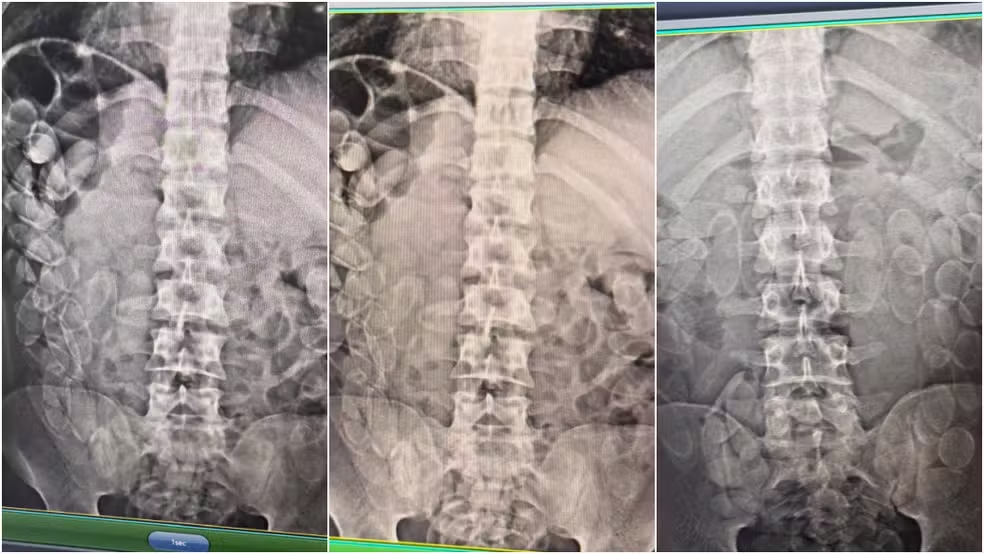

Durante a fiscalização, três homens, de 21, 27 e 31 anos, foram detidos transportando aproximadamente 5 kg de pasta base de cocaína. Segundo a polícia, a droga foi encontrada camuflada em um frasco de condicionador de cabelo, na cueca de um dos suspeitos e o restante os suspeitos confessaram que haviam engolido.

À polícia, os bolivianos informaram que ingeriram cerca de 100 cápsulas cada e que a droga seria levada para São Paulo, onde receberiam pelo transporte. Os suspeitos foram encaminhados à Santa Casa de Corumbá e, após expelir as cápsulas, serão levados à Delegacia da Polícia Federal.